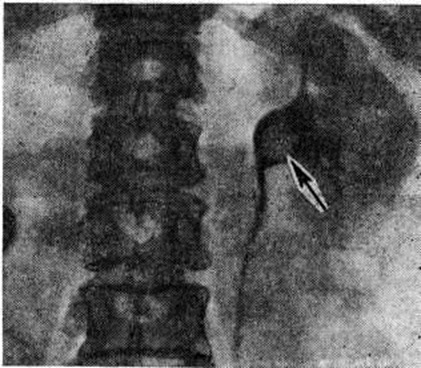

Рентгенологические метод является основным в диагностике Почечнокаменная болезнь Он позволяет выявить не только наличие камней, но и установить их форму, величину, локализацию, структуру, а также получить представление об изменениях в анатомо-функциональном состоянии почек и мочевых путей. Исследование начинают с обзорной рентгенографии брюшной полости, начиная от ThXl до лонного сочленения. Обнаружение на обзорной рентгенограмме тени, подозрительной на конкремент, не требует дифференциальной диагностики только в случае коралловидного камня, являющегося слепком чашечно-лоханочной системы (рисунок 2). Камни почечных чашечек представляют собой их слепки или имеют неправильную, округлую форму; камни почечной лоханки часто округлые или треугольные; камни мочеточника — цилиндрической, веретенообразной или неправильной формы. При аномалиях мочевых путей конкремент может находиться вне обычной локализации почек и других органов мочеполовой системы. Обнаружение камня на снимке зависит от его размеров, химический состава и локализации. Наиболее интенсивное изображение дают оксалаты, затем камни смешанного состава и фосфаты. Оксалаты имеют шиповидные, фестончатые контуры и напоминают тутовую ягоду. Коралловидные камни чаще всего компактны, но могут быть слоистыми, как и остальные конкременты смешанного состава, иногда они достигают гигантских размеров. Слоистое строение камней на рентгенограммах обусловлено различной проницаемостью для рентгеновского излучения составляющих их солей. Около 10% камней с низким атомным весом (ураты, белковые, цистиновые и ксантиновые камни) не видны или дают неотчётливую тень. Особенно трудно выявить камни, проецирующиеся на костный скелет (ребра, поперечные отростки позвонков, крестцово-подвздошные сочленения). Для их обнаружения производят прицельные снимки в косых и атипичных проекциях, томо или зонографию. Томография (смотри полный свод знаний), применяемая самостоятельно или в сочетании с контрастными исследованиями, показана при недостаточной подготовке больного к рентгенологическое исследованиям, почечной колике, сопровождающейся парезом кишечника, или при малых размерах камней. Поскольку при Почечнокаменная болезнь довольно часто конкременты самопроизвольно отходят из чашечно-лоханочной системы, они могут проецироваться по ходу мочеточника паравертебрально, имеют тенденцию задерживаться над одним из его анатомических сужений. Наиболее важные сведения о принадлежности выявленной тени к мочевым путям, о локализации камня, вызванных им нарушениях функции почек, уродинамики, анатомического состояния мочевых путей (гидрокаликоз, пиелэктазия, гидроуретеронефроз — расширение чашечек, лоханки, мочеточника и почки) выявляются при экскреторной урографии (рисунок 3, б) с предварительной обзорной рентгенографией (рисунок 3, а). Она позволяет установить вид лоханки (открытая или закрытая, внутрипочечная или внепочечная), состояние лоханочно-мочеточникового сегмента (смотри полный свод знаний: Пиелография). Обычно рентгенопозитивный конкремент определяется в мочевых путях, но иногда его изображение перекрывается, как бы тонет на фоне контрастированной мочи, особенно при небольшом камне или малой интенсивности его изображения. При рентгенонегативных камнях виден дефект наполнения мочевых путей (в том числе и лоханки) с чёткими контурами (рисунок 4). В отличие от опухоли лоханки в косых проекциях вокруг камня сохраняется ободок контрастного вещества. Обычно при камнях лоханки, достигающих в диаметре 3 сантиметров и более, наблюдаются пиелэктазия и гидрокаликоз. Произведённые в процессе экскреторной урографии телевизионная пиелоуретероскопия в сочетании с кинематографией или видеомагнитофонной записью изображения позволяют оценить нарушения тонуса и моторной функции верхних мочевых путей при камнях, отличить спастические, функциональный процессы от органических. Если спустившийся в мочеточник камень частично закрывает его, то отмечаются расширение мочеточника и лоханки (пиелоуретерэктазия) выше уровня расположения конкремента. На экскреторных урограммах, произведённых во время почечной колики, выявляется увеличенная почка с усиленным нефрографическим эффектом без контрастирования чашечно-лоханочной системы и мочеточника — так называемый большая белая почка. Такая рентгенологическое картина указывает, что функция почки сохранена. При длительной полной блокаде камнем (более 3—4 недель) функция почки из-за атрофии снижается и может полностью утрачиваться. На экскреторных урограммах, произведённых после почечной колики, иногда наблюдается проникновение контрастированной мочи за пределы мочевых путей, а также лоханочно-почечный рефлюкс. Ретроградную пиелоуретерографию с жидким контрастным веществом или кислородом производят только при значительном снижении функции почек, при сомнении в диагнозе, особенно в тех случаях, когда при экскреторной урографии не выявляется рентгенонегативный камень. Рентгенографию мочеточника после введения в него катетера производят в прямой и косой проекциях. Если при этом тень, подозрительная на камень, на обоих снимках находится рядом с катетером или сливается с его тенью, то диагноз Почечнокаменная болезнь не вызывает сомнений. Тень, не относящаяся к мочеточнику, определяется на некотором расстоянии от катетера. На ретроградных пиелограммах с жидким контрастным веществом небольшой концентрации рентгенонегативные камни выявляются в виде дефекта наполнения. Особенно демонстративными такие камни становятся при пневмопиелорентгенографии или пневмопиелотомографии (рисунок 5). С помощью ретроградной уретерографии удаётся выявить рентгенонегативный камень в мочеточнике, верхние границы дефекта при этом имеют вогнутую форму (рисунок 6).